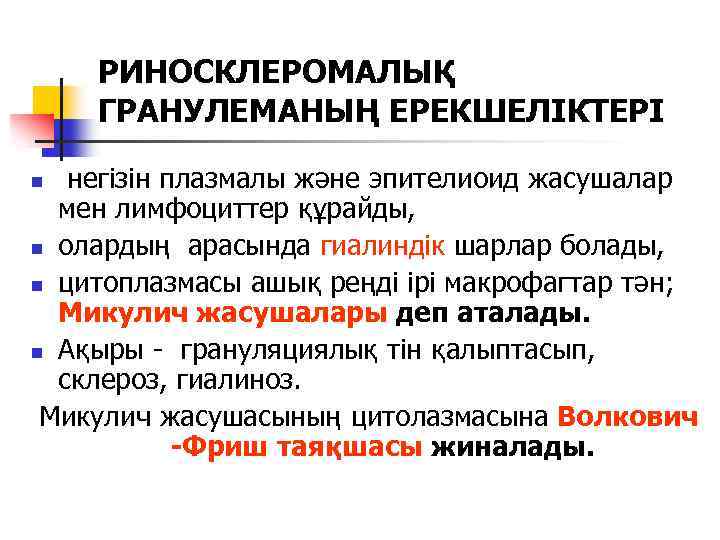

РИНОСКЛЕРОМАЛЫҚ ГРАНУЛЕМАНЫҢ ЕРЕКШЕЛІКТЕРІ негізін плазмалы және эпителиоид жасушалар мен лимфоциттер құрайды, n олардың арасында гиалиндік шарлар болады, n цитоплазмасы ашық реңді ірі макрофагтар тән; Микулич жасушалары деп аталады. n Ақыры - грануляциялық тін қалыптасып, склероз, гиалиноз. Микулич жасушасының цитолазмасына Волкович -Фриш таяқшасы жиналады. n